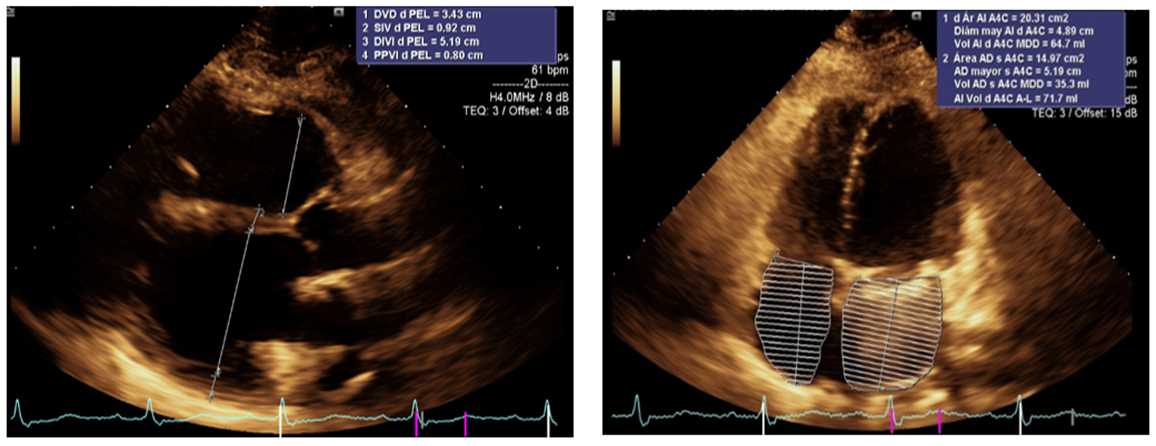

The second case is a course of worse prognosis of aA 47-year-old female patient with a family history of a deceased brother due to heart failure and a living sister with the same clinical syndrome who has currently undergone a transplant. She had a cardiovascular history of mitral valve replacement in 2016 and is currently undergoing treatment for heart failure. She attended the cardiology consultation for the first time due to dyspnea when climbing stairs that had been developing for six months. She denied DPN or orthopnea. Cardiovascular physical examination revealed rhythmic heart sounds of adequate intensity. S1 and S2 were unchanged, and S3 or S4 showed a prosthetic click in the mitral valve focus of adequate intensity, with no additional acoustic phenomena, and no pleuropulmonary syndrome. As part of the protocol, diagnostic aids were requested. A chest x-ray showed a mitral valve prosthesis in position, grade II cardiomegaly, and an electrocardiogram showed complete right bundle branch block. A transthoracic echocardiogram showed a dilated left ventricle with a 57mm end-diastolic diameter and 44mm end-systolic diameter, with a normofunctioning prosthesis with a mean gradient of 3.8 mmHg and an area of 1.5 cm2. A dilated left atrium had an indexed volume of 32 mm. Generalized hypokinesia, with reduced systolic function of 36%, and LVEF due to longitudinal global strain of 40%. Moderate secondary functional TR with an indexed ring of 37 mm. Treatment was started with loop diuretics, ACEIs, beta-blockers and VKAs. Due to family history, a genetic test was requested, which documented a mutation in the LMNA gene, on chromosome 1q22: c.568c> t (p.arg190trp), which allowed establishing the prognosis and prompt referral to the heart failure service with a path to heart transplant, however with progressive clinical presentation (persistence of dyspnea, NYHA functional class II and episodes of DPN), with a new echocardiogram two years later with respect to the initial one that reported dilated cardiomyopathy with reduced biventricular function, normofunctional mechanical mitral prosthesis, LVEF of 25% by biplane Simpson, right ventricle with dilated diameters, severe tricuspid regurgitation secondary to annulus dilation. Heart failure treatment was adjusted by adding complete neurohumoral blockade, with sequential dose adjustment, electrocardiogram in sinus rhythm QRS 140 ms RBBB morphology, ergospirometry was requested to objectively determine functional class, patient with MAGGIC prognosis of 10 points, mortality at 1 year of 3.9% and at 3 years of 10.2, with rapid progression of the disease despite complete treatment of heart failure for which the patient was taken to ICD for prevention of sudden cardiac death, currently undergoing heart transplantation.

Figure 3: Apical 4-chamber axis showing dilation of the left atrium

Figure 4: Apical 2-chamber axis showing the ejection fraction and end-diastolic volume of the left ventricle, the acoustic shadow generated by the mechanical mitral prosthesis is observed (red arrow)